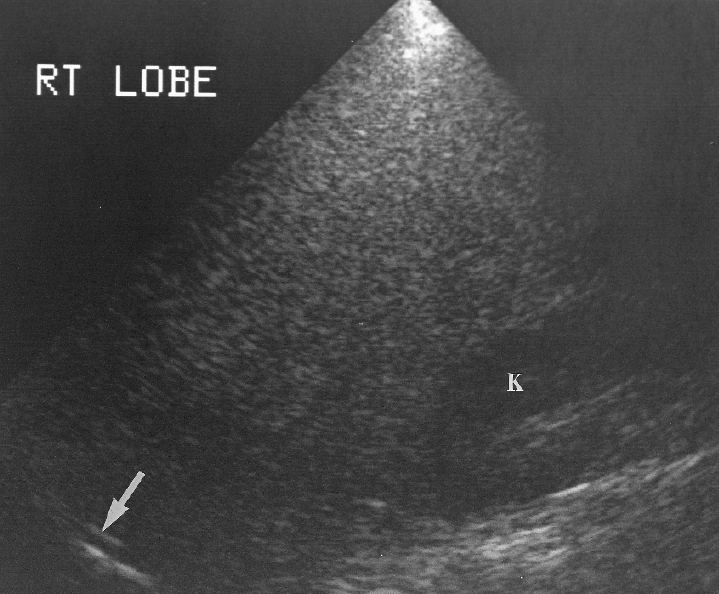

Explain the procedure of a liver exam.

Begin doing a full sweep through the liver. Starting sagittal,

slightly to the left of midline. Change to a transverse view and sweep

up and down the left lobe from a subcostal approach. Look in

transverse through the right lobe subcostally or

intercostally.

What is the liver protocol?

Sagittal

Left lobe (wedge)

Left lobe W/ caudate

lobe

Left lobe W/ aorta

Right lobe W/ IVC

Right lobe W/

dome

Right lobe W/ Morrison’s pouch

Liver/kidney

comparison

Right lobe W/ gallbladder

Transverse

Left lobe W/ portal

vein

Left lobe W/ ligament teres

Right lobe W/ hepatic

veins, IVC

Right lobe W/ dome

Right lobe W/ portal

veins

Right lobe W/ kidney and gallbladder